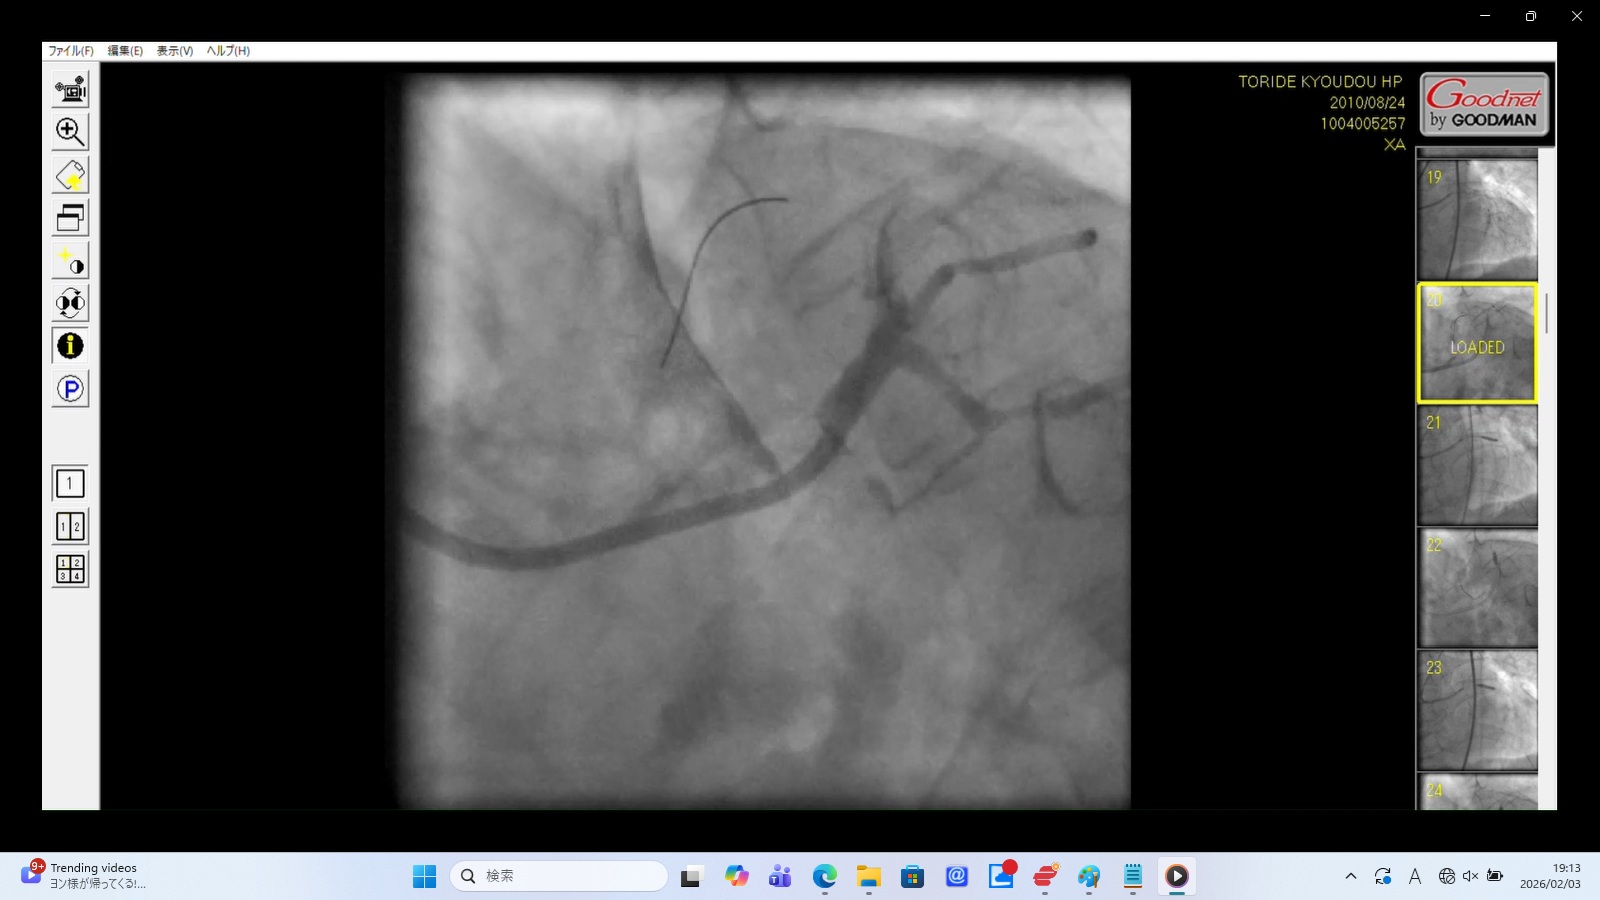

Finding: Contrast media flows abnormally slowly into the LAD, expanding in a non-anatomical fashion.

Interpretation: Strong evidence of coronary artery dissection. The catheter appears to be wedged in a false lumen, and the "slow flow" represents the physical peeling of the vessel wall layers in real-time.